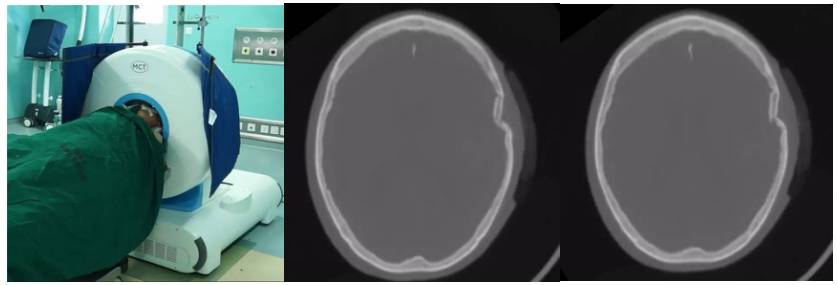

急诊室脑梗塞移动CT床旁脑部扫描

脑科ICU脑出血移动CT床旁脑部扫描

脑科手术室脑损伤移动CT床旁脑部扫描